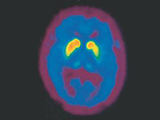

Parkinson’s disease is the second most common neurodegenerative brain disorder. It is estimated that 7-10 million people are affected worldwide; however, this number is likely to rise significantly in the next years due to an ageing population. Most patients are diagnosed around the age of 60. The disease can, however, occur, especially in genetic cases at a very early age: up to 10 % of cases are diagnosed before the age of 40. In general, men are more likely to be diagnosed with Parkinson’s disease than women.